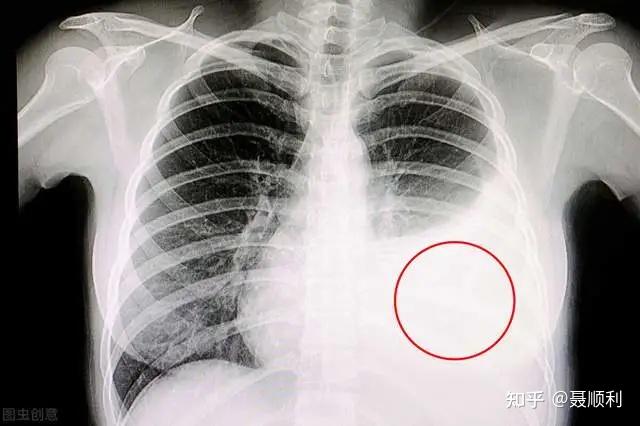

肺部图片胸片,胸片图片肺大泡

胸片图片肺大泡

胸片正常图片

正常胸片和肺炎胸片图

正常胸片和异常胸片